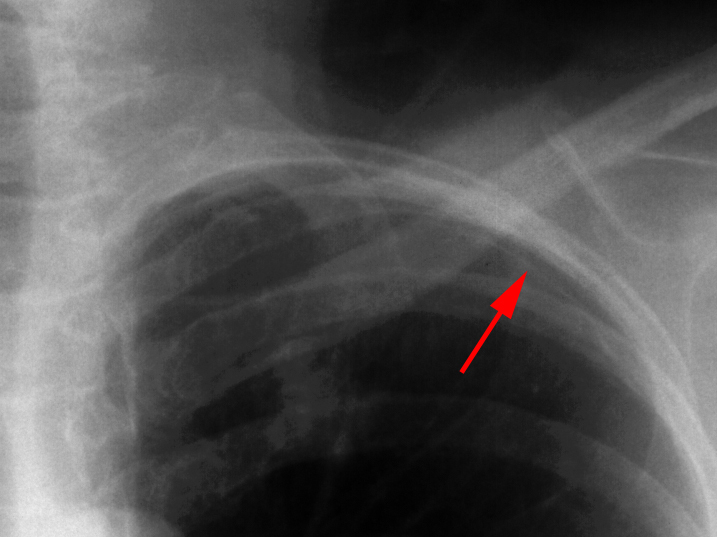

Apicolateral pneumothorax

Appears as a thin, white pleural line with no lung markings beyond. The presence of lung markings beyond this line, though, does not exclude pneumothorax. This is especially true in the patient with parenchymal disease which may alter the compliance of affected lobes, making their collapse more difficult to detect radiographically. Parenchymal disease may also make visualization of the pleural line more difficult or impossible.